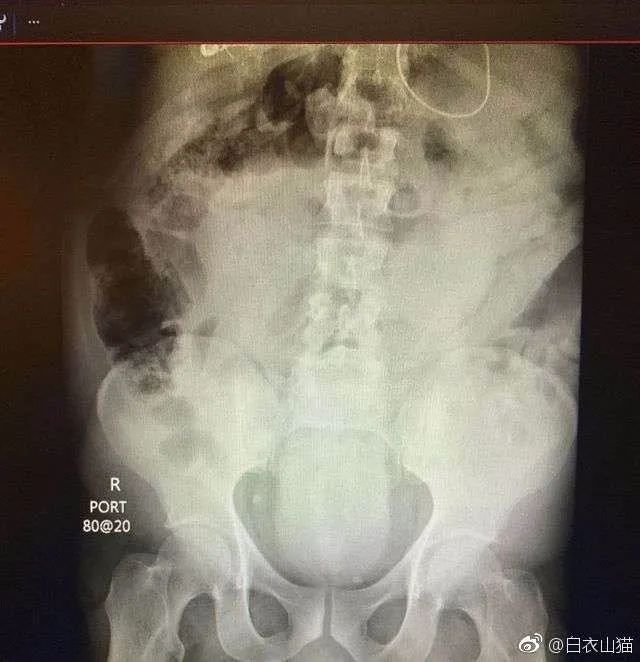

第4天,他拉不出大便。剧烈呕吐,剧烈腹痛。实在熬不住了,就去了一个大医院,但是,他隐瞒了自己把黄鳝塞进菊花的病史。

医生给他检查的时候,发现已经有腹膜炎症状,怀疑肠梗阻,拍了个片子,就是上面那个片子:一条大黄鳝在肚子里。

考虑到他已经有腹膜炎的症状,说明肠子已经有个地方破了。只能动手术了。

把肚子打开后,发现大肠破了个洞,黄鳝的头,就在那个洞里。他肚子里都是大便。他的肠子水肿很厉害。黄鳝堵住了大肠,肠梗阻,导致大肠坏死穿孔了。

这种情况下,就是把大肠的洞补起来,洞也长不好。只能造瘘了。也就是在破了个洞的地方把大肠割断,肚皮上挖个洞,大肠拖到肚皮外面,以后的大便从肚皮上排出来。等肚子里炎症消退后,再把大肠放回肚子里接回去。这样他要动2次手术。